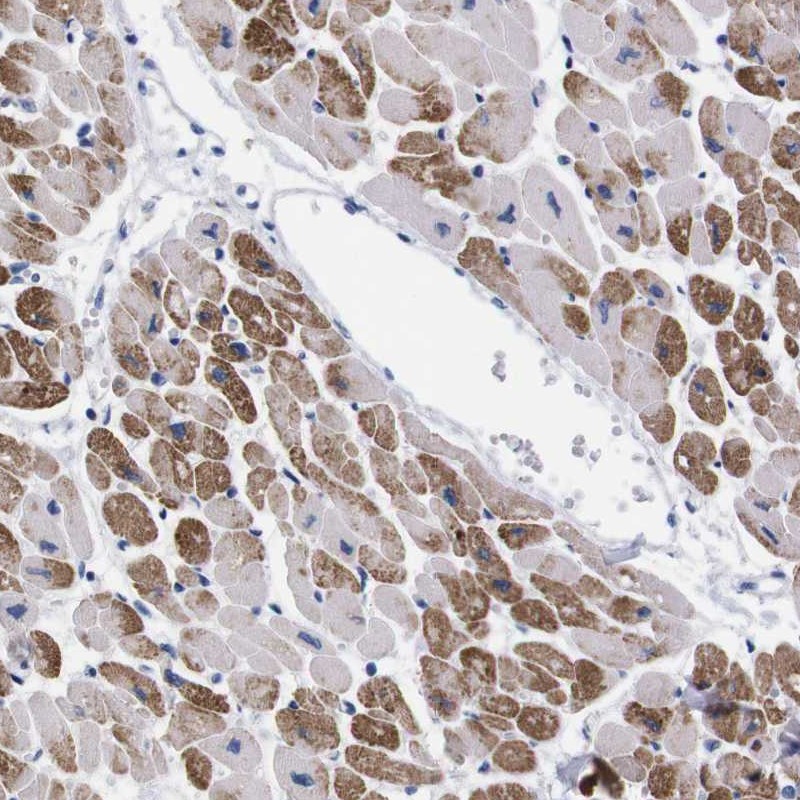

Immunohistochemical staining of human heart muscle shows strong cytoplasmic positivity in myocytes.